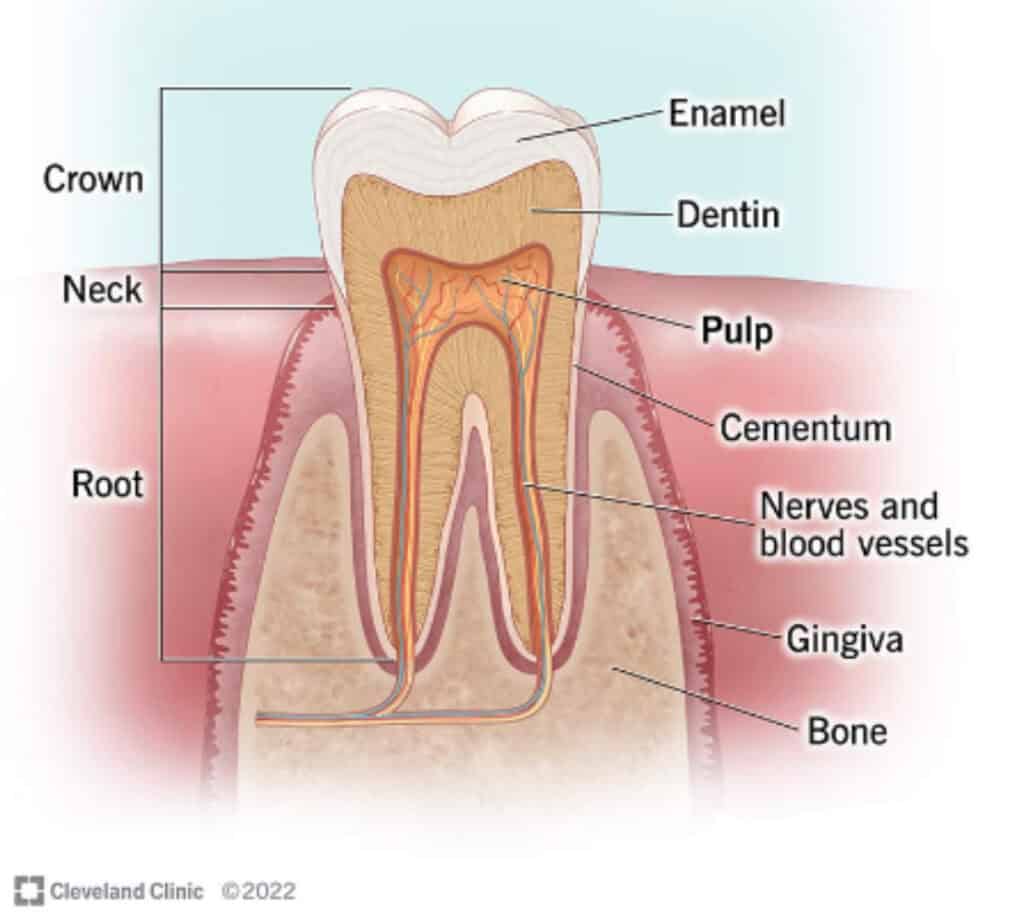

Quick pause to understand the anatomy of a tooth.

The outer layer of our tooth, the enamel, is the strongest and most mineralized layer. Enamel is thickest and strongest at the chewing surface of the tooth and gets thinner and more porous (weaker) as it tapers to the root by the gumline. The middle layer of the tooth is dentin, which is less mineralized and more porous, with the porosity getting greater as you get deeper into the dentin. Understandably, this layer is the more sensitive layer of the tooth. These pores are in direct communication with the pulp, the innermost layer of the tooth. The pulp has no mineral content. It is a soft tissue layer that contains blood vessels, the nerve of the tooth, and lymphatic tissue. The outer portion of the pulp contains construction cells called odontoblasts. These cells are essentially the handyman of the tooth that can, with sufficient mineral building blocks, lay down reparative and reactionary dentin in response to pathogens, irritants, and injury.

When dental caries (tooth decay) is in the strong enamel outer layer, it is “incipient” and reversible. Maximizing topical remineralization and minimizing demineralization can heal it. If a cavity reaches the dentin layer, it is no longer reversible. If confined to the outer third of dentin, it could potentially be arrested (stop the growth), but this will take a VERY disciplined approach to shift the demineralization/remineralization balance. If the dental caries reaches past the outer third, into the more porous part of the dentin layer, effects on the dental pulp are greater with higher risk of irreversible damage to the pulp, which can ultimately lead to an infected tooth. Restoration is necessary and immediate improvement of the demineralization/remineralization balance is critical..

Remineralization from inside the teeth. The most important factor in internal tooth mineralization is a nutrient dense diet! If our levels of Vitamins D3 and K2 are sufficient, then odontoblasts inside the pulp tissue of our teeth will have the calcium and phosphorus building blocks they need to build and lay down reactionary and reparative dentin tooth structure to protect the pulp of the tooth from injury.